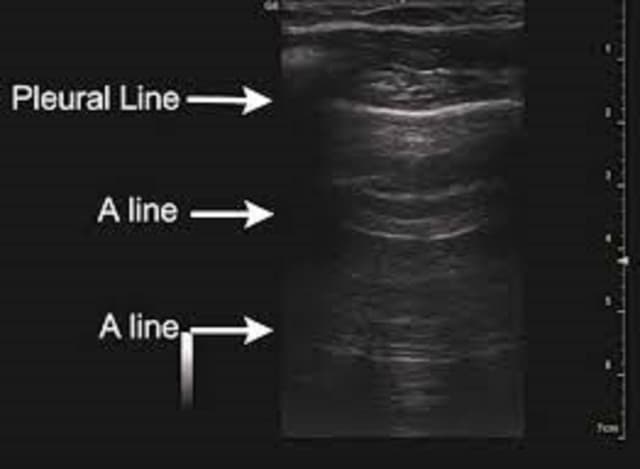

Siêu âm phổi và những ứng dụng thú vị trong chẩn đoán

Siêu âm màng phổi là một phương pháp thăm dò không xâm lấn, dễ sử dụng, được sử dụng rộng rãi trên lâm sàng. Trong vài năm gần đây, siêu âm cũng đã trở thành một cánh tay đắc lực cho việc chẩn đoán nhanh các bệnh lý hô hấp: tràn dịch màng phổi, tràn […]